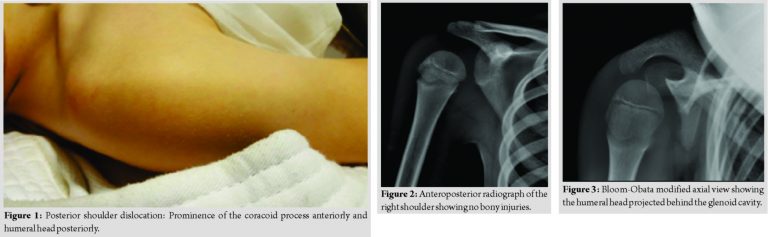

A 9-year-old boy presented with pain and a complete inability to use his right arm after being thrown while practicing judo. His right upper limb was held adducted and internally rotated. External rotation was limited. Acromion and coracoid process were prominent anteriorly. Humeral head was palpable posteriorly with a flattened anterior shoulder (Fig. 1). There was no evidence of vascular or nerve injury, particularly the axillary nerve.

The anteroposterior radiograph of the shoulder seemed normal (Fig. 2). However, several radiological signs were in favor of the diagnosis: The lightbulb sign (head of the humerus was in the same axis as the shaft) and the rim sign (widening of the glenohumeral space >6mm). The Bloom-Obata modified axial view showed a humeral head that was displaced behind the glenoid cavity (Fig. 3). Shoulder computed tomography (CT)-scan confirmed the posterior shoulder dislocation and the absence of scapular or proximal humeral fracture (Fig. 4).